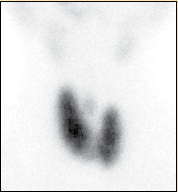

Se inicia el estudio por pérdida de peso y edema. Se solicitaron estudios de laboratorio, y se reportó glucosa sérica de 93 mg/dL; urea sérica, 44 mg/dL; creatinina sérica, 0.49 mg/dL; colesterol total, 100 mg/dL; c-HDL, 32 mg/dL; c-LDL, 40 mg/dL; triglicéridos, 140 mg/dL; calcio corregido con la albúmina, 10.4 mg/dL; fósforo, 4.9 mg/dL; nitrógeno ureico, 20.6 mg/dL. Perfil hormonal: T4 libre 7.7, ng/dL; TSH, < 0.005 µUI/dL; cortisol, 16.10 µg /dL; HbA1c, 6.3%. Con este reporte, se decide realizar gammagrama tiroideo, en el cual se encontró glándula tiroides en situación anatómica normal, ligeramente aumentada de tamaño con predominio para el lóbulo tiroideo derecho, con hipercaptación del radiotrazador con un patrón homogéneo congruente con bocio tóxico difuso (figura 2). Con estos resultados, la paciente fue diagnosticada con hipertiroidismo apático por enfermedad de Graves. Se inició tratamiento con propranolol a dosis de 40 mg cada 8 horas y metimazol 15 mg cada 12 horas.

El hipertiroidismo apático puede presentarse por cualquier causa de hipertiroidismo. La etiología puede variar desde tiroiditis, bocio nodular tóxico o enfermedad de Graves. En nuestra paciente se realizó el diagnóstico diferencial con otras entidades que cursan con tirotoxicosis. En este caso, los datos clínicos y el gammagrama tiroideo con bocio difuso e incremento de la captación permitieron descartar los cuadros de tiroiditis (tiroiditis dolorosa de Quervain, tiroiditis indolora esporádica), los cuales presentan una hipocaptación tiroidea. Asimismo, el adenoma tóxico y el bocio multinodular tóxico pueden detectarse en la exploración física y el gammagrama tiroideo muestra una captación focal con supresión de la tiroides circundante al adenoma o múltiples focos de captación con focos suprimidos en el bocio multidodular13-14. Otro posible diagnóstico diferencial es el de hipotiroidismo provocado por tiroiditis de Hashimoto en su variante clínico-patológica de “hashitoxicosis”, la cual se presenta con características similares a un hipertiroidismo por enfermedad de Graves, inclusive con el mismo patrón de captación en la prueba con yodo radiactivo; sin embargo, dicha entidad clínica termina por evolucionar a hipotiroidismo permanente, situación que no sucedió con la paciente del presente caso15.